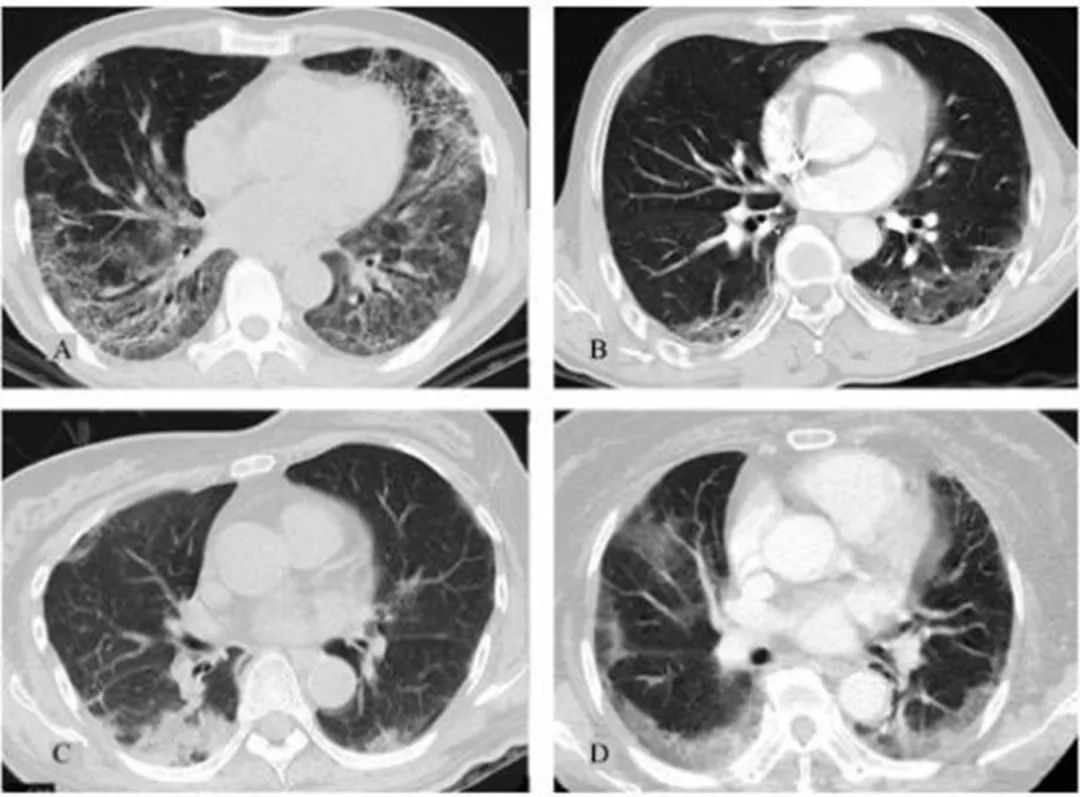

抗MDA5抗体(抗黑色素瘤分化相关基因5抗体)主要与皮肌炎(DM)相关,尤其是无肌病性皮肌炎(ADM),高度提示快速进展性间质性肺病(RP-ILD),病情凶险,死亡率高。病人皮肤表现典型,如手掌丘疹、皮肤溃疡、甲周红斑等。抗体滴度与疾病活动度相关:高滴度抗体提示更高风险的RP-ILD和更差的预后。治疗监测:治疗有效时抗体滴度可能下降,持续高滴度需警惕病情反复或恶化。预后评估:抗体阳性患者需早期强化免疫抑制治疗(如糖皮质激素联合环磷酰胺或他克莫司)。

透景生命即将推出肌炎抗体谱(流式荧光发光法),单项和多重相得益彰,不仅能够同时检测抗MDA5、抗Tif-Y抗体和其他MSAs,而且出具定量报告。经比对发现,与ELISA定量试剂具有很好的相关性(附图))。